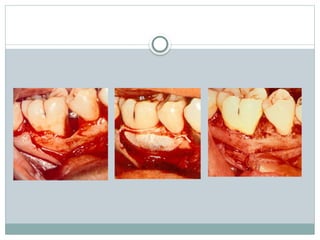

SURGICAL TREATMENT

Root resection

Hemisection

Reconstruction

Extraction

Root resection

A root resection or amputation is done when

one of a tooth's damaged roots is removed while

keeping the healthy root or roots in place.

Hemisection

 It is splitting of a two-rooted tooth into two separate

portions

 This process has been called bicuspidization or

separation as it changes the molar into two

separate roots.

 It is most likely to be performed on mandibular

molars with buccal and lingual class II or III

furcation involvements

Tunnel preparation

Regeneration